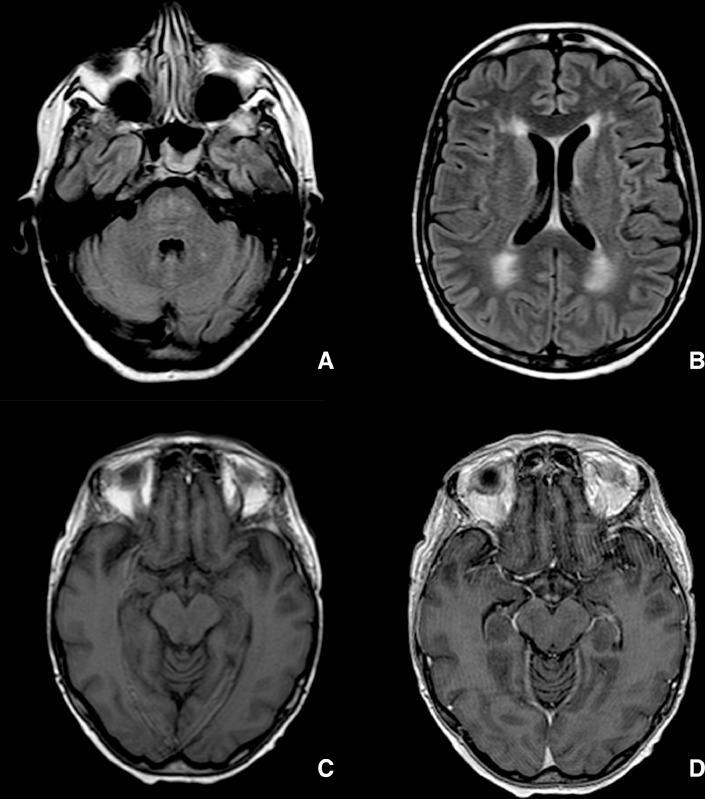

Graft-versus-host disease (GVHD) is an immune triggered process leading to severe immune dysregulation and organ dysfunction until death and it is one of the worst medical complications after a transplant. Patients with GVHD may have several neurological alterations: during this acute severe phase there is coexistence of various and nonspecific neurological symptoms. We are reporting a case of a 53 year old woman with severe GVHD after bone marrow transplant with acute neurological signs and symptoms. MRI study showed findings consistent with Posterior reversible encephalopathy syndrome and Wernicke encephalopathy.

移植物抗宿主病(GVHD)是一种由免疫触发的过程,会导致严重的免疫失调和器官功能障碍,直至死亡,它是移植后最严重的医学并发症之一。患有移植物抗宿主病的患者可能会出现多种神经学改变:在这个急性重症阶段,会同时存在各种非特异性神经症状。我们报告了一例53岁女性患者,在骨髓移植后发生严重移植物抗宿主病,并伴有急性神经体征和症状。磁共振成像(MRI)研究显示的结果与后部可逆性脑病综合征和韦尼克脑病相符。